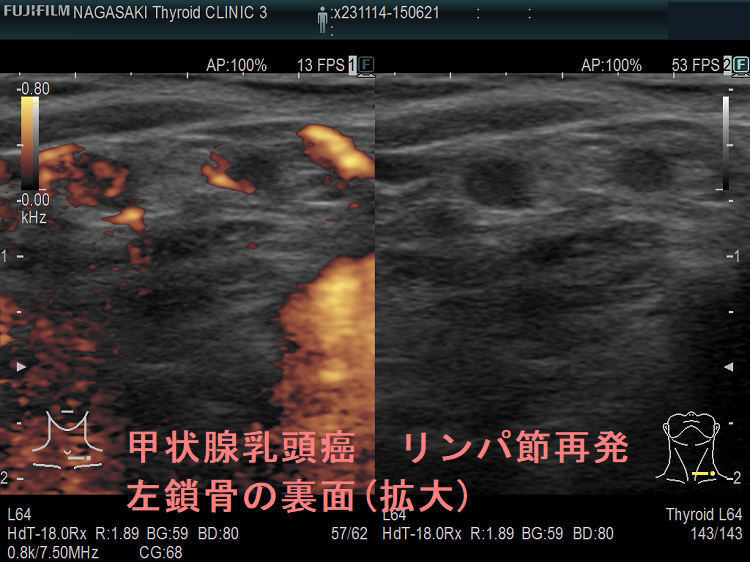

甲状腺乳頭癌鎖骨の裏 リンパ節転移再発

甲状腺乳頭癌 リンパ節再発 左鎖骨の裏面

甲状腺乳頭癌 リンパ節再発 左鎖骨の裏面(拡大)